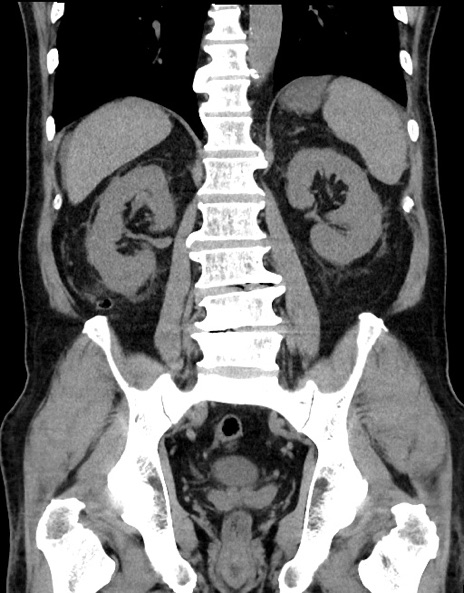

症例15(冠状断像)

【症例】70歳代男性

【主訴】腹痛

【現病歴】今朝から腹痛あり。全体的に痛い。特に左上の方。排ガスが今日はない。冷や汗が出る。

【既往歴】直腸癌術後

【身体所見】左側腹部〜上腹部に圧痛あり。腹膜刺激症状明らかなではない。軽度反跳痛。左下腹部に術後瘢痕あり。

【データ】WBC 7700、CRP 0.02